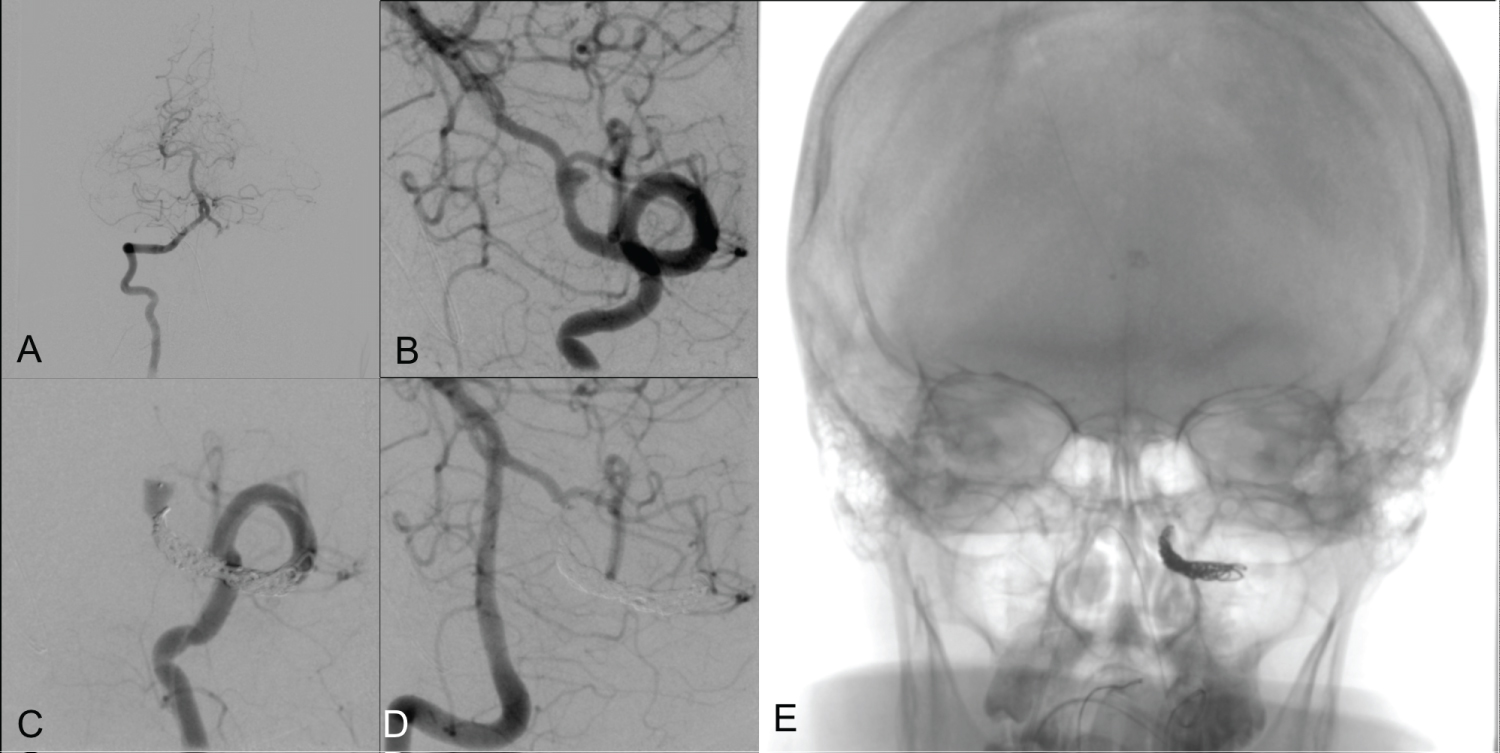

The diagnostic angiogram revealed codominant vertebral arteries, with a 4.5 mm ruptured left vertebral artery fusiform dissecting aneurysm extending approximately 20 mm in the V4 vertebral artery distal to the PICA origin (Figure 1A and Figure 1B). Additionally, it confirmed the presence of an unruptured left superior hypophyseal artery aneurysm measuring 3.26 × 2.3 mm, bilateral posterior communicating arteries with the left significantly larger than the right, a normal left P1 posterior cerebral artery, and a hypoplastic right P1 posterior cerebral artery.

Figure 1: Diagnostic Cerebral Angiogram. (A) Right vertebral artery angiogram with crossing filling of the contralateral verbal artery filing to the left PICA; (B) 4.5 mm ruptured left vertebral artery fusiform dissecting aneurysm stretching 20 mm in the left vertebral artery distal to the PICA origin; (C) Left vertebral artery angiogram showing angiographic occlusion of the left vertebral artery sparing the LPICA origin with the use of WEB and coils; (D) Right vertebral artery angiogram showing the left PICA crossfilling from the right vertebral artery and angiographic occlusion of the left vertebral fusiform aneurysm; (E) Anterior/posterior native fluoroscopy showing the location of the WEB and coils in the proximal V4/ distal V3 vertebral segment. View Figure 1

Given the aneurysm rupture, the persistence of collateral flow from the anterior circulation through the posterior communicating arteries (PCOM), and the lack of feasible open surgical options, the decision was made to sacrifice the left vertebral artery. A 4.5 × 3 mm WEB device was deployed to occlude the vertebral artery proximal to, but not covering, the PICA origin. Two coils were then placed to complete the occlusion of the left vertebral artery. Post-procedure, the left PICA and all its branches were well visualized, filling from the contralateral vertebral artery (Figure 1C and Figure 1D). Aspirin 81 mg was administered to reduce the risk of stump embolization.